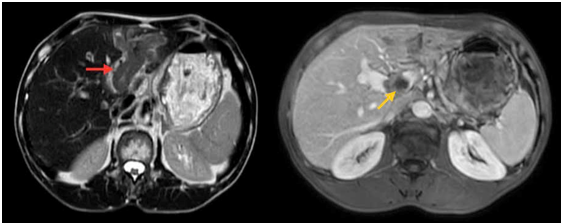

Hình 1. Hình ảnh chụp cộng hưởng từ ổ bụng

Hình ảnh gan biến đổi hình thái, bờ không đều. Nhu mô gan trái có đám tổn thương sau tiêm ngấm thuốc không đều, tổn thương xâm lấn theo tĩnh mạch cửa nhánh trái vào thân chung gây huyết khối nhánh trái và thân chung tĩnh mạch cửa (mũi tên vàng) tạo đám tổn thương kích thước khoảng 55x77mm (mũi tên đỏ)